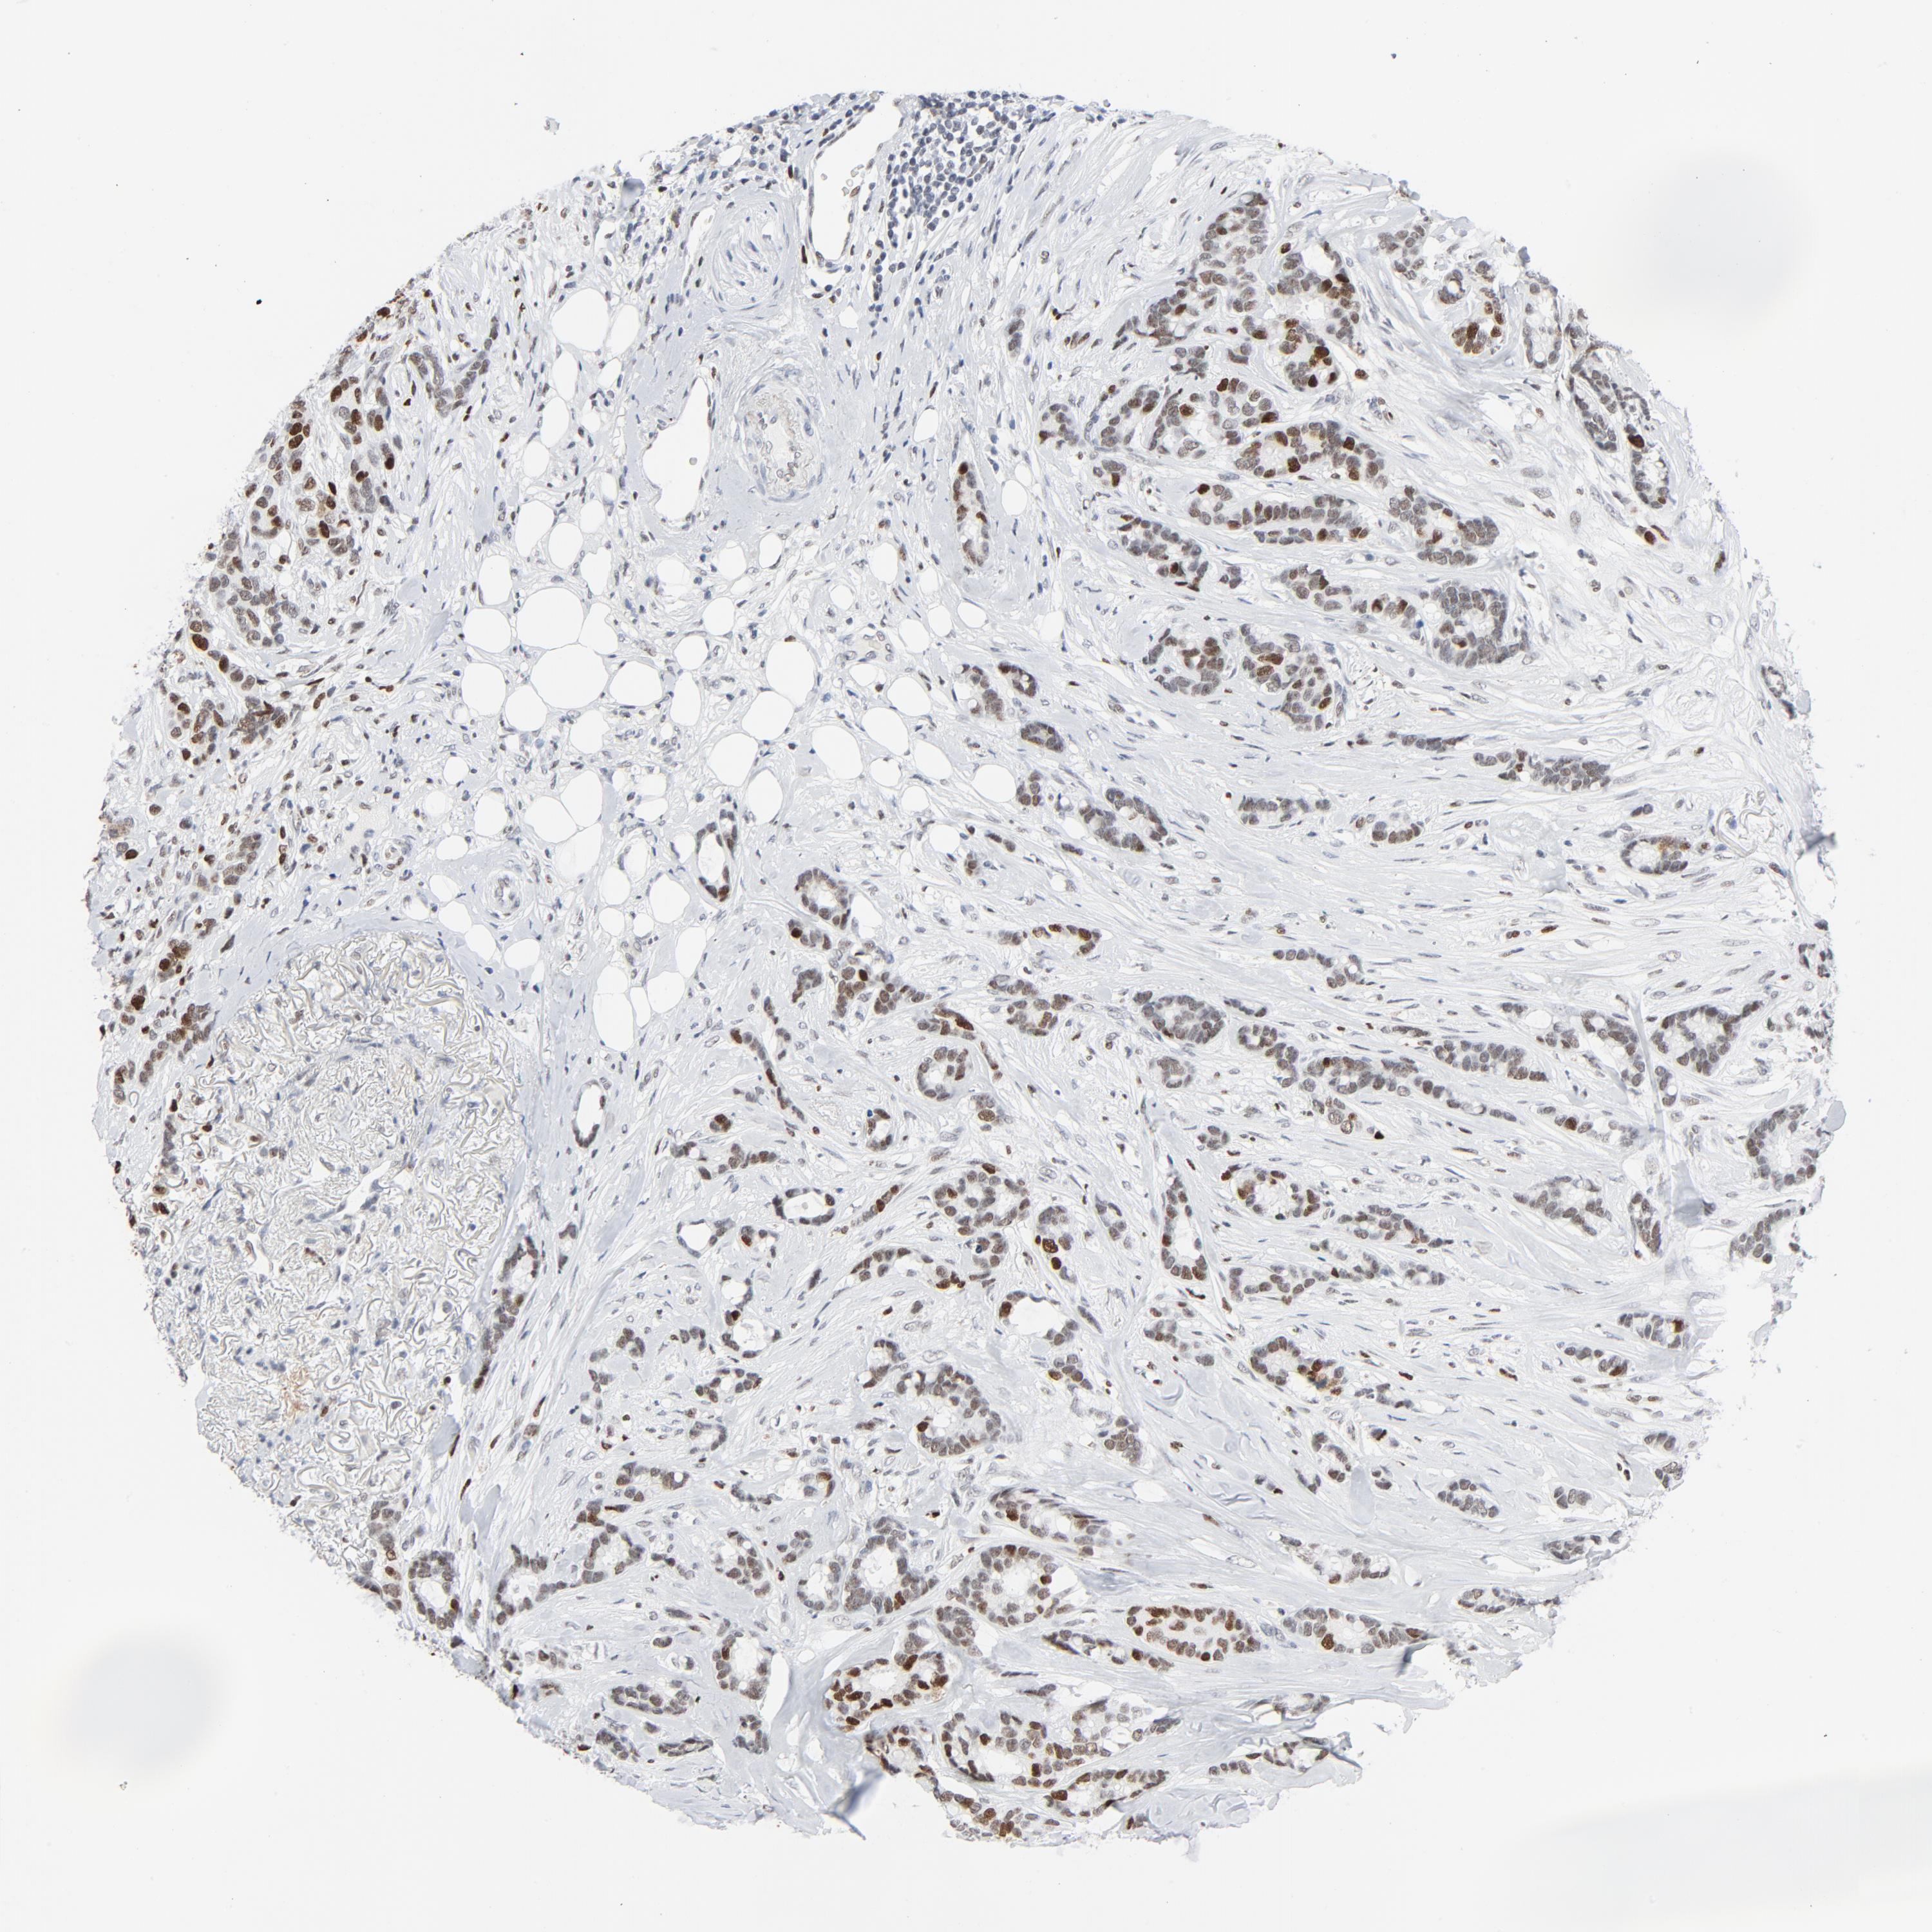

BRCA TCGA BRCA VALIDATION PROTEIN EXPRESSION

ANTIBODIES

AND

VALIDATION